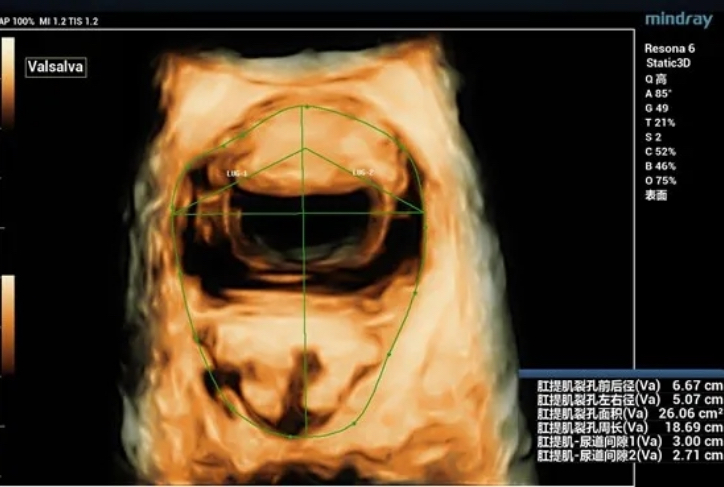

During maximal Valsalva maneuver, the bladder neck is 14mm below the pubic symphysis , the lowest point of bladder is 16.9mm below, the uterus is 7.3mm above and the rectum is 10.4mm below. The levator ani hiatus is 26.06cm2 (see Figure 2).

Figure 5 Three-dimensional ultrasonic measurement of levator ani hiatus area